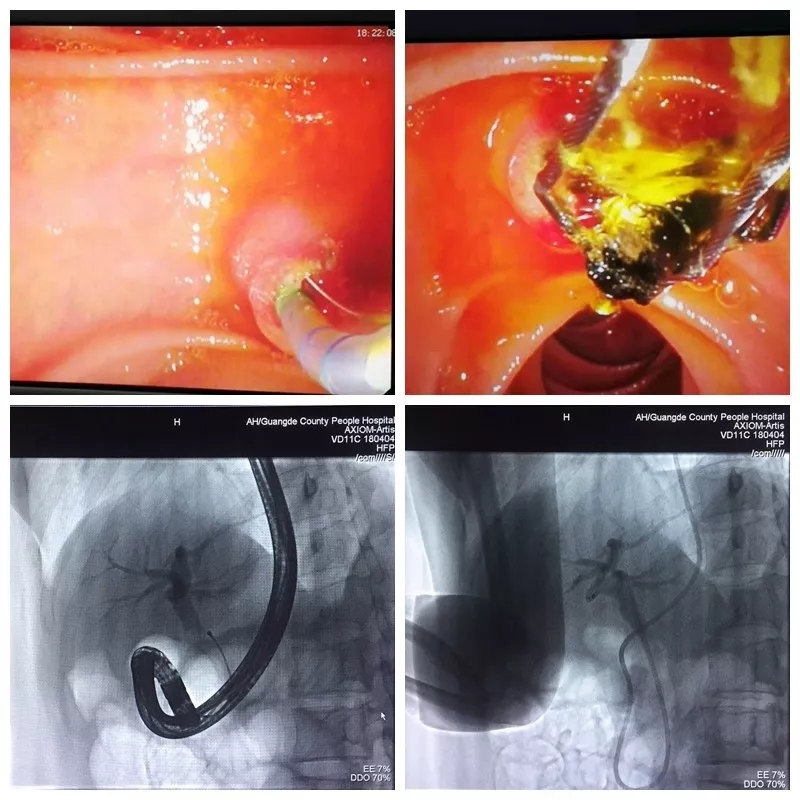

近日我院消化内科在贾玉良院长的带领下,成功开展了我院首例ERCP!

患者为一名33岁女性, 原有胆囊结石病史,因腹痛收住外五科,入院后经MRCP检查示:1、胆囊炎、胆囊及胆囊管多发结石。2、胆总管下段结石。为行ERC取石治疗转入消化内科。

经充分的术前检查、讨论,与患者进行细致的术前谈话后,患者及家属同意接受ERC取石治疗, 7月18日,贾玉良院长带领消化内科医生为患者行“ERC+网篮取石术、胆道清理术+ENBD”治疗胆总管结石,通过网篮取石、胆道清理后造影充盈缺损影消失,沿导丝插入鼻胆引流管于胆总管中段,固定鼻胆管于鼻翼,接负压引流袋后见胆汁流出,X线见鼻胆管定位良好。

整台手术流畅、顺利,非常成功,术后患者安返病房,诉有腹部疼痛、恶心呕吐,经抗炎、抑酶抑酸治疗,术后4天缓解,现患者无腹痛,无其他不适,已康复出院。